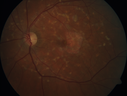

62 year old man does not notice much vision. He has no history of vision loss in either eye. He has family members with glasses but does not know of any eye problems in the family. VA OD: Dcc20/20-1 PH20/16 NccJ3 VA OS: Dcc20/40 PH20/25 NccJ5

Stargardt's Macular Dystrophy514 views62 year old man with good vision00000